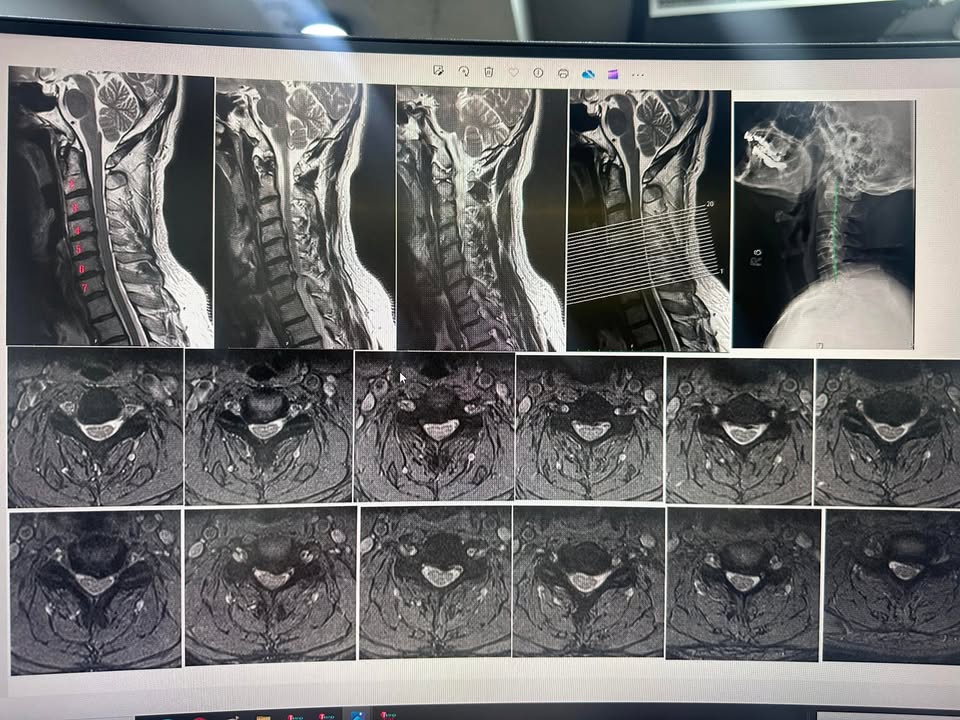

判斷:這些影像顯示的是患者的頸椎MRI檢查,分別呈現了不同的切片和視角。以下是影像的初步解讀:

1. 頸椎側面觀(矢狀面):

• 影像顯示了C3到C7(第3到第7頸椎)的狀況。特別是在和C5-C6跟C6-C7處,有明顯椎間盤的變化或突出,壓迫到脊髓或神經根,造成相應的臨床症狀如頸部疼痛或上肢麻木。

2. 橫切面影像:

• 下方的橫切面影像展示了不同高度的頸椎橫斷面。可以看到在部分影像中,C6/C7明顯脊髓周圍的空間變窄,因為椎間盤突出或骨質增生導致的脊椎管狹窄。

3. 病理變化:

• 第二張影像中特寫展示了可能的椎間盤突出,特別是在C5-C6和C6-C7處,這些部位的椎間盤突出可能引起脊髓或神經壓迫,進而導致臨床症狀。

評估:有壓迫!但還沒有到手腳無力,開刀暫時緩緩,雖然患者已經表示大醫院已經準備叫他開刀